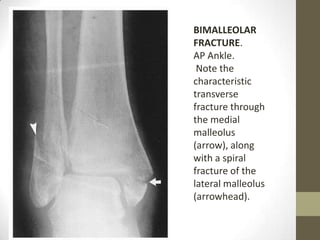

BIMALLEOLAR

FRACTURE.

AP Ankle.

Note the

characteristic

transverse

fracture through

the medial

malleolus

(arrow), along

with a spiral

fracture of the

lateral malleolus

(arrowhead).